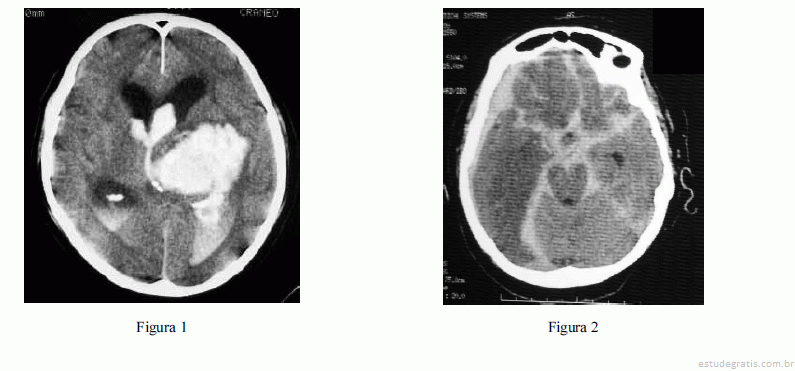

Com relação às figuras 1 e 2 acima, que mostram os exames de imagem de dois pacientes distintos, julgue os itens que se seguem.

Caso a figura 1 apresente o resultado de exame de imagem de um paciente idoso, a principal hipótese diagnóstica será de angiopatia amiloide devido à localização típica da lesão.Comentários